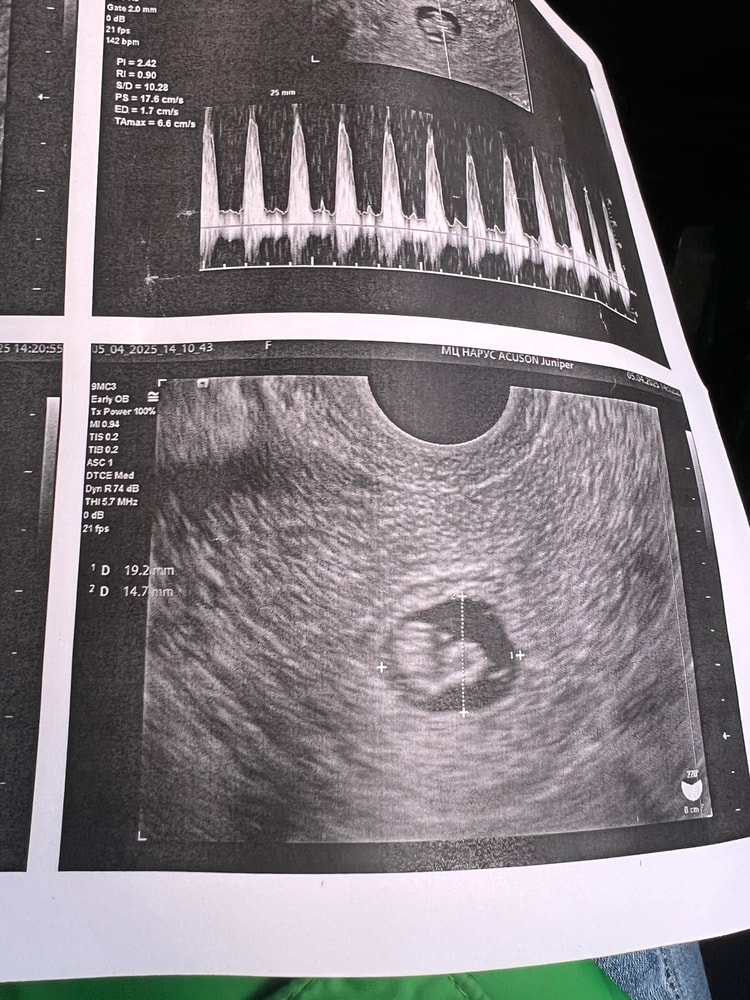

УЗИ, почти 8 недель, эмбрион растер - а ПЯ не очень

На прошлой неделе было ПЯ Свд 12, ктр 5, сб 108

На этой неделе Свд 17, ктр 11,7 мм, сб 140

узистка подписала олегогидроамнион? Или маловодие в последствии, как я понимаю.

предполагает, что может быть из за двурогой матки ПЯ чуть отстает, не знаю.

gular yahyayeva, добрый день, 12 апреля была на узи - ктр 17,8 мм и ПЯ 26. Оно так же отстает на неделю, но я предпочитаю думать, что у малявки такая студия-хрущевка) сб 162 удара, развитие идет) в эту субботу тоже иду на узи и 12 мая на скрининг 🤞🤞🤞